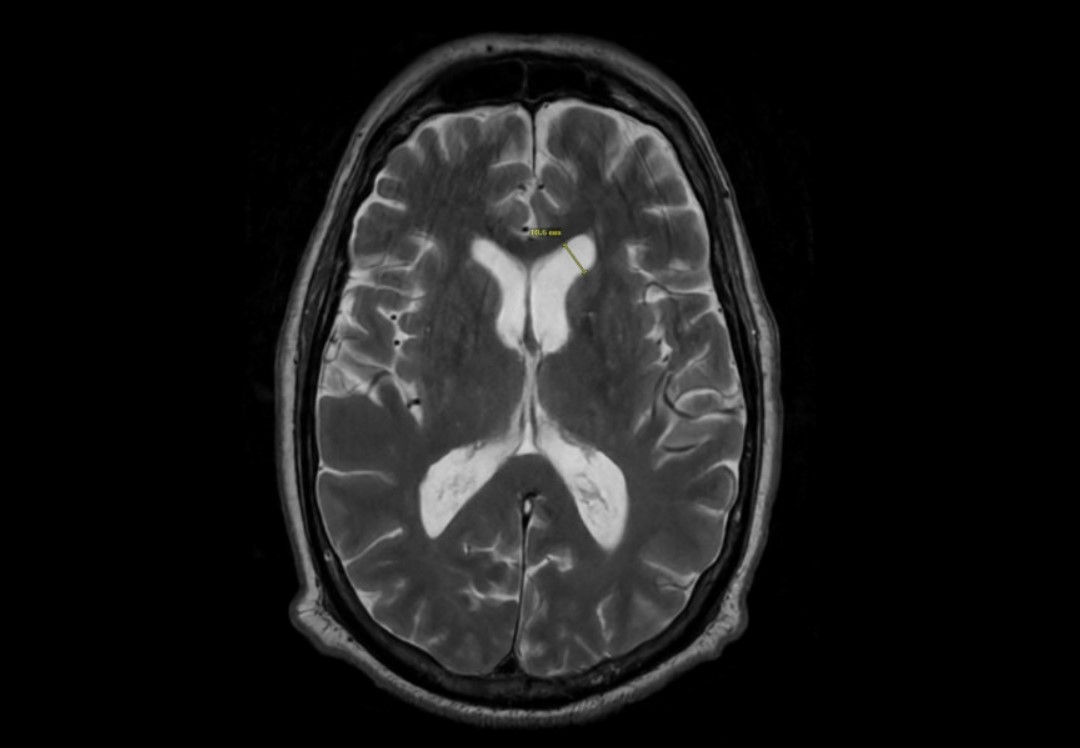

Case Presentation: This case report outlines the case of a 76 year-old male who presented with bacterial meningitis secondary to an infected intrathecal baclofen pump, but initial lumbar puncture cerebrospinal fluid (CSF) did not demonstrate pleocytosis. Patient endorsed worsening headache, vomiting, and bilateral lower extremity weakness 6 days prior to admission. He was immediately started on empiric coverage with vancomycin, ampicillin, and ceftriaxone. He had a brain magnetic resonance imaging which found leptomeningeal enhancements and ventriculitis raising concerns for meningitis. He continued to worsen with development of hallucinations and seizures. He had CSF collected on hospital day 7 and day 11. Initial CSF obtained on day 7 of admission at L4-L5 (delayed due to availability of interventional radiology) demonstrated 1-2 WBC, >600 protein, 132 glucose, negative meningitis/encephalitis panel, negative culture, and eventually negative UCSF metagenomics panel. CSF obtained via direct aspiration of his baclofen pump on day 11 demonstrated 283 WBC, 75 protein, 8 glucose and culture eventually grew pseudomonas. He was discharged on 28 days of ceftazidime after removal of his baclofen pump with recovery back to his baseline.